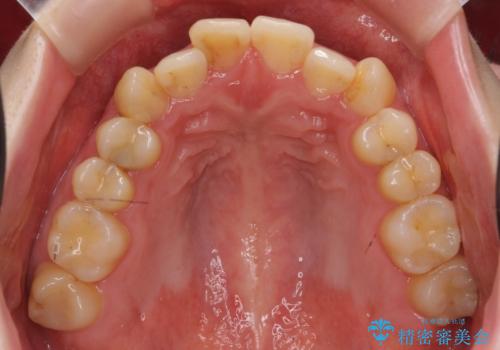

犬歯のねじれ 上の歯が引っ込んでいる

- 前歯の並びを気にして来院。

インビザラインで、上の前歯をやすり掛けして並べました。